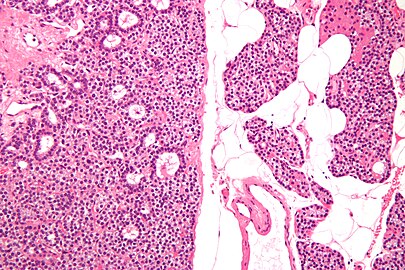

Parathyroid Adenoma

A parathyroid adenoma is a benign tumor of the parathyroid gland. It generally causes hyperparathyroidism; there are very few reports of parathyroid adenomas that were not associated with hyperparathyroidism.[1]

Before surgery is attempted, the affected glandular tissue must be located. Though the parathyroid glands are usually located on the back of the thyroid, their position is variable. Some people have one or more parathyroid glands elsewhere in the neck anatomy or in the chest. About 10% of parathyroid adenomas are ectopic, located not along the back of the thyroid but elsewhere in the body, sometimes in the mediastinum of the chest.[9] This can make them difficult to locate, so various imaging techniques are used, such as the sestamibi scan, single-photon emission computed tomography (SPECT), ultrasound, MRI,[9] and CT scans.[9][11] sometimes parathyroid adenomas can be ablated by ethanol injection, laser or radiofrequency guided by ultrasound.